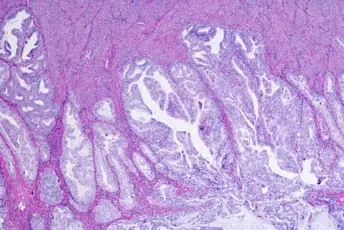

子宫内膜癌诊断指南

学习关于这种类型的子宫癌的基础知识被诊断和分阶段,包括测试类型。